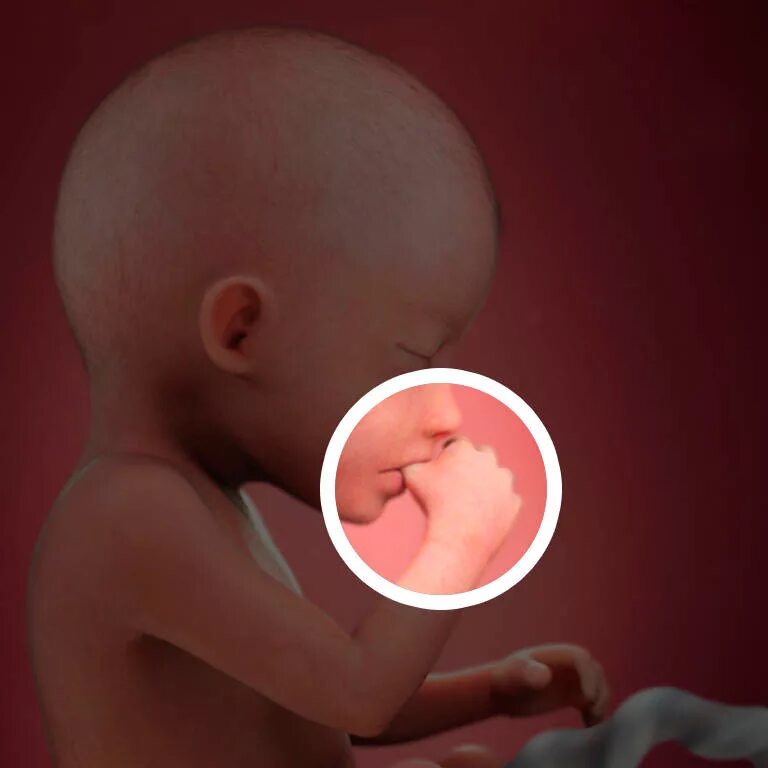

Через 20 недель